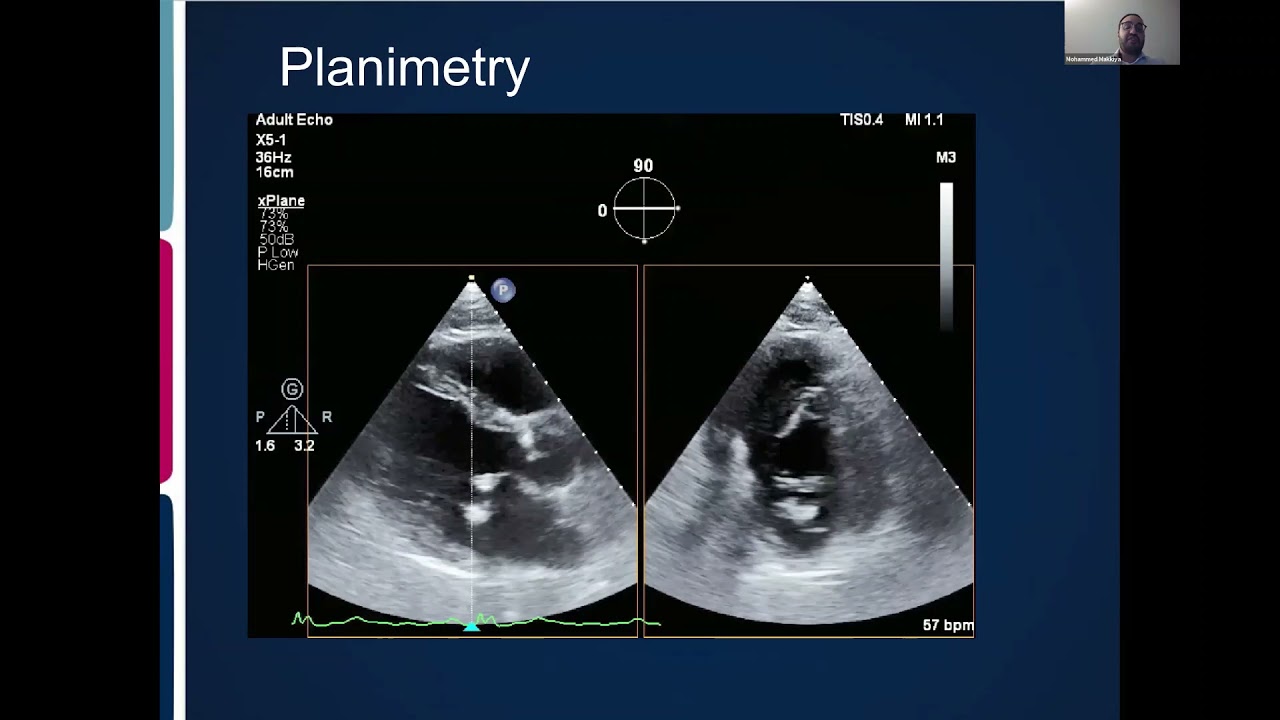

Diagnosis is confirmed with echocardiography, which uses ultrasound to visualize cardiac structures and blood flow. Echocardiography also helps determine the severity of the disease by measuring the mitral valve area. ECG recordings and chest X-ray may show signs of left atrial enlargement.